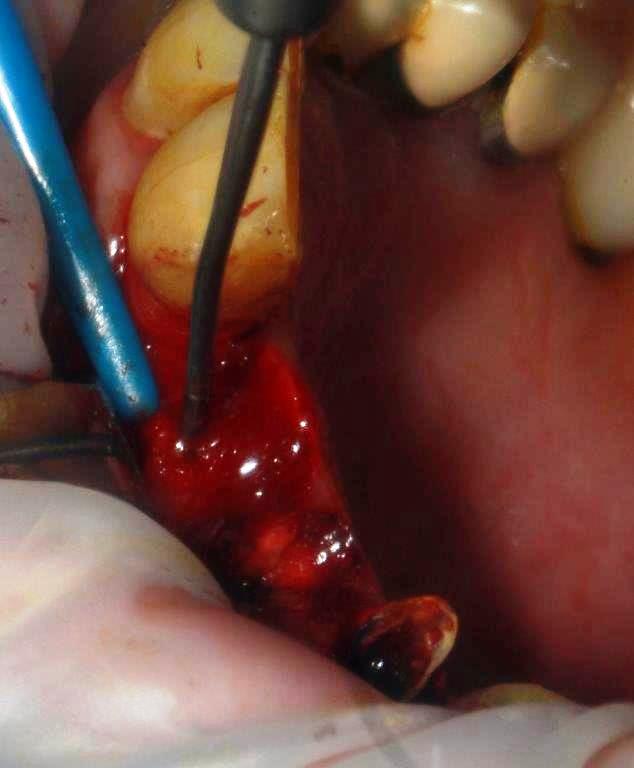

-Alors comme je suis de cet avis je me lance, avec un cas tout bête d'expansion, patient 70 ans, non fumeur, porteur d'un bridge 12/13/14, 13 et 14 en fin de vie, difficile de laisser le patient sans dents, et pas envie d'une EIIM, je décide de tenter la dépose/ repose du bridge, et de poser un implant en 12 os fin bonne qualité, je n'ai pas le scan ici je vous le passerai ultérieurement.

la difficulté est de corriger l'axe

ostéotome 1mm